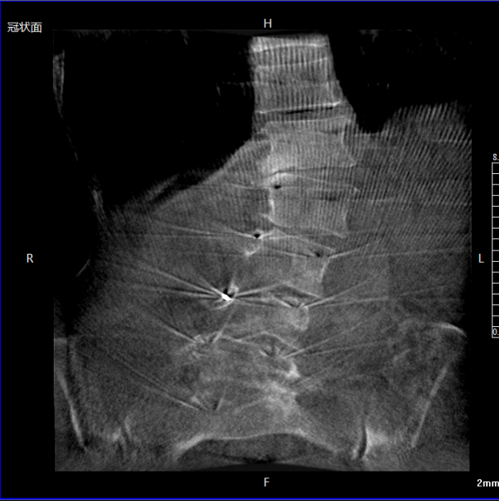

Качество изображений 3D C-дуги: ключевые факторы высокоточной визуализации

Качество визуализации 3D C-дуги имеет решающее значение для современной ортопедии, травматологии и малоинвазивной хирургии позвоночника. Несмотря на внешнее сходство многих систем по техническим характеристикам, уровень оптимизации качества 3D-изображений C-дуги может значительно различаться, что напрямую влияет на точность хирургических манипуляций, достоверность реконструкции и принятие интраоперационных решений. Понимание инженерных, физических и системных факторов, влияющих на качество изображения, является критически важным для хирургов, радиологов и биомедицинских инженеров.

Высокоточная визуализация обеспечивает точную установку винтов, достоверную оценку позвонков и надежную регистрацию навигации. Это снижает количество интраоперационных корректировок и послеоперационных осложнений.

4.2 Травмы таза и вертлужной впадины

Точная репозиция переломов и корректная установка имплантов зависят от качества 3D-реконструкций. Интраоперационная точность напрямую влияет на результат лечения и снижает риск повторных операций.